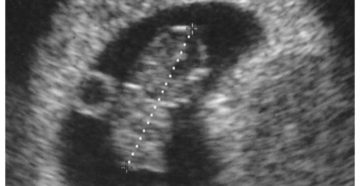

Основные задачи УЗИ на 8 неделе беременности Практически каждый определенный период во время беременности требует…

8 неделя беременности — В положении 1 8 неделя беременности: что происходит с малышом и…